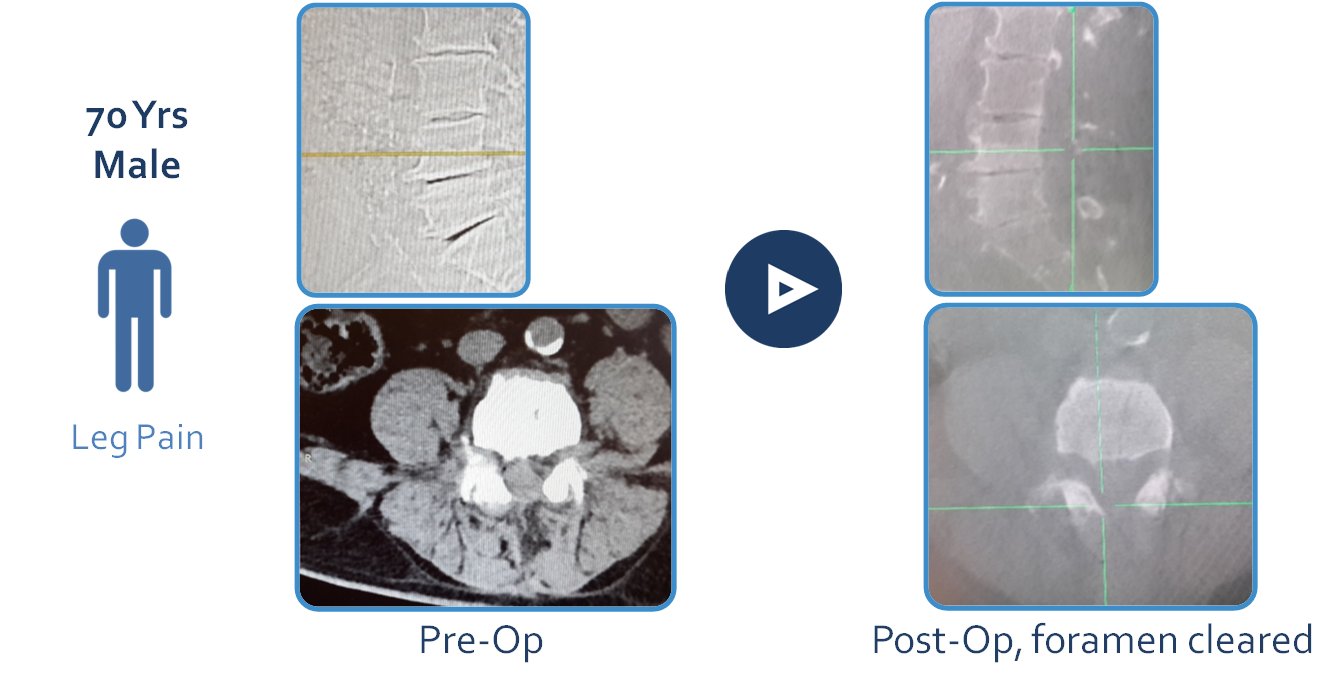

CASE #5 – Lumbar- 70 year old male suffering from leg pain